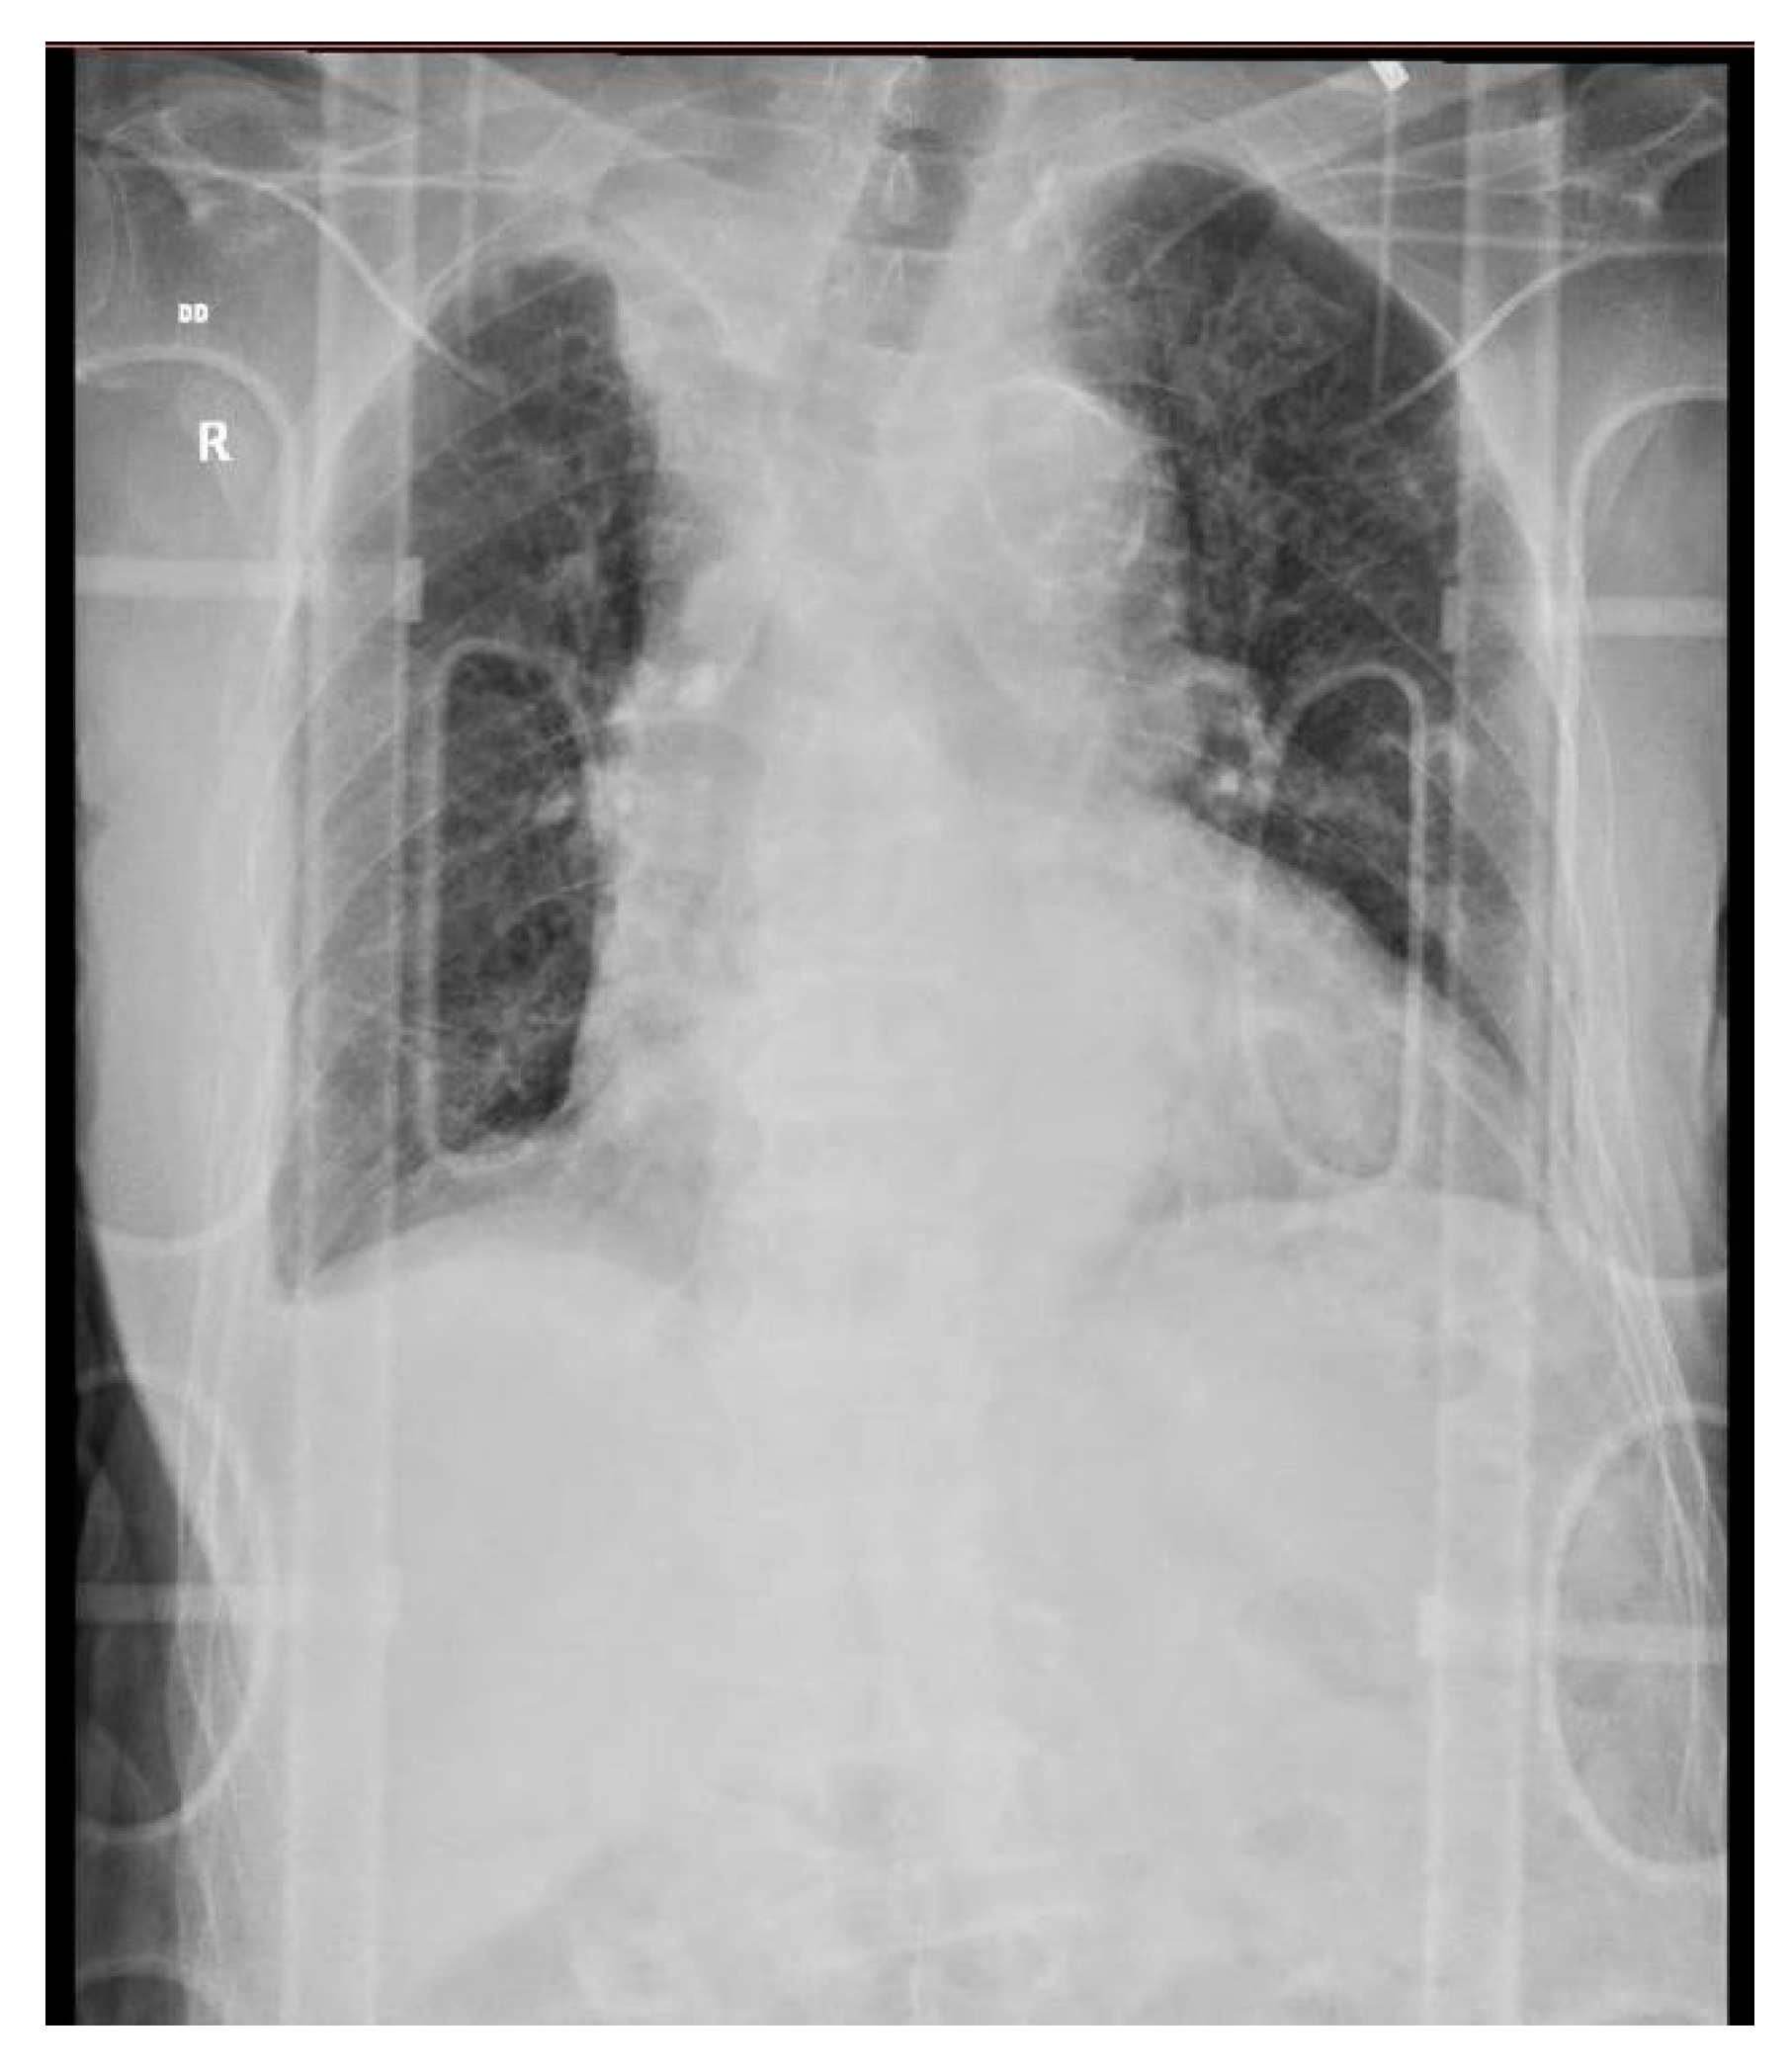

The next day, before surgery, the patient underwent a chest X-ray (Figure 5) and blood work (leucocyte 10.93 × 103/uL; haemoglobin 8 g/dL; Htc 24%; serum creatinine 2.07 mg/dL; urea 100 mg/dL). A left femur intramedullary nail was placed (Figure 6), and one unit of blood was transfused.

Figure 5. Chest X-ray upon arrival as per pre-surgery protocol, anteroposterior incidence. Description: diffuse, bilateral, reticular pattern. Possible right upper lobe atelectasis. Increased area of projection of the heart and mediastinum. Minimal right pleural effusion. No signs of rib fractures.